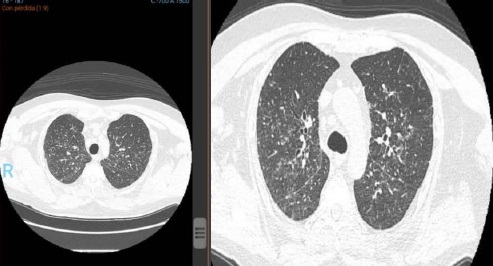

La sarcoidosis pulmonar se caracteriza por varios hallazgos en la tomografía computarizada de alta resolución (TCAR). Estos incluyen linfadenopatía hiliar y paratraqueal bilateral bien definida, opacidades nodulares y micronodulares con distribución perilinfática. Los nódulos son redondeados y suelen tener un tamaño de 2 a 4 mm. También se observa el agrandamiento y calcificación de los ganglios linfáticos hiliares bilaterales. Las calcificaciones pueden presentar diferentes aspectos, como amorfo, puntiforme (parecido a una palomita de maíz) o similar a una cáscara de huevo. La distribución perilinfática de las lesiones micronodulares es el patrón parenquimatoso más frecuente. Con el tiempo, estas lesiones pueden fusionarse y formar macronódulos y conglomerados similares a masas, con la presencia de pequeños nódulos satélites alrededor de las masas conglomeradas, lo que se conoce como “signo de galaxia”.

En la TCAR se pueden encontrar otros hallazgos menos frecuentes, como cambios fibróticos con opacidades lineales y bronquiectasias por tracción, opacidades parcheadas en vidrio esmerilado, consolidación parcheada del espacio aéreo (alveolitis sarcoide o sarcoidosis alveolar), opacidades reticulares lineales aisladas, halo inverso o signo del atolón. La sarcoidosis pulmonar también muestra un patrón de atenuación en mosaico debido a la afectación granulomatosa o fibrosis de las vías respiratorias pequeñas, lo cual puede estar asociado con obstrucción en las pruebas de función pulmonar. El atrapamiento de aire es común pero no específico de la sarcoidosis y puede estar presente en cualquier etapa radiográfica de la enfermedad. Se detectan anomalías traqueobronquiales en la TC, con engrosamiento y estenosis de la pared bronquial, que se correlacionan con los hallazgos broncoscópicos.

En la tomografía computada de tórax en ventana pulmonar se identifica un patrón micronodular con distribución perilinfática y difusa en ambos hemitórax. Este hallazgo se acompaña de un engrosamiento peribronquial notable, así como de opacidades en vidrio deslustrado, que predominan en las zonas subpleurales y en las regiones posteriores de ambos pulmones.